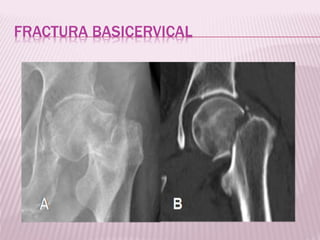

FRACTURA BASICERVICAL

 El trazo de fractura coincide con el plano de

fusión de la base del cuello en la superficie

interna del macizo trocantereo.